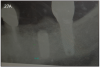

Dental implants are the best option to replace missing teeth. However, complications during treatment may arise, such as failure to integrate or bone loss while in function. (Figure 25)

Figure 25 – Radiograph showing significant bone loss around the implant, one year after placement

Figure 25